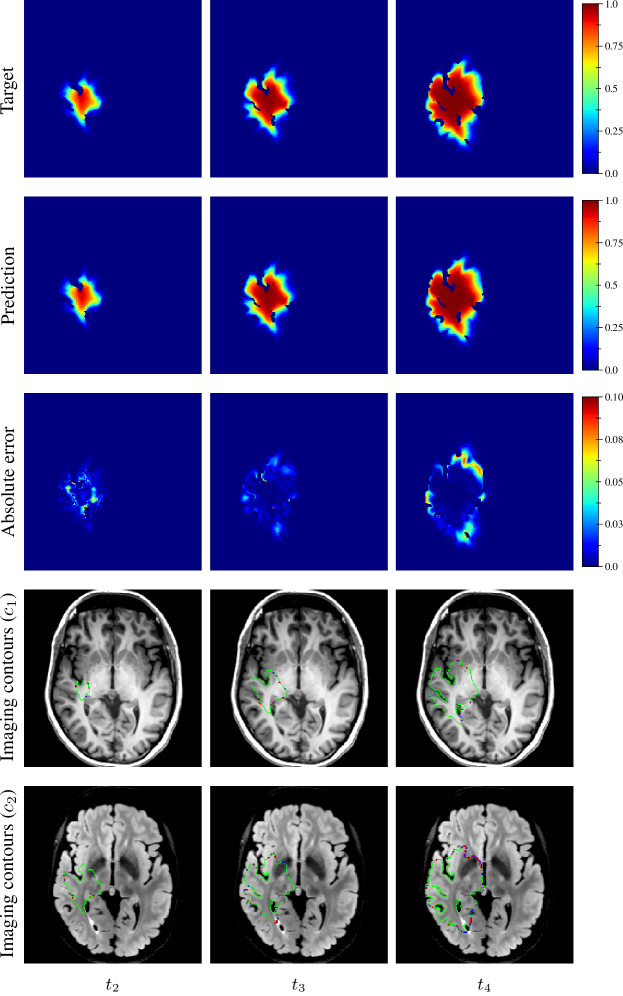

The distribution of the mean absolute error computed over the test set between the true and estimated tumour cell distributions at time t2subscript𝑡2t_{2} within the c>0.01𝑐0.01c>0.01 contour is summarised by a boxplot in Figure 7 (1st plot). The corresponding median value was 9.58×1039.58E-39.58\text{\times}{10}^{-3}. Boxplots of the Hausdorff distance and ASSD distributions computed over the test set between the true and estimated imaging contours at time t2subscript𝑡2t_{2} for threshold values c1=0.80subscript𝑐10.80c_{1}=0.80 and c2=0.16subscript𝑐20.16c_{2}=0.16 are provided in Figure 8 (1st plots). An example of true and estimated tumour cell density distributions at time t2subscript𝑡2t_{2} from the test set is depicted in Figure 9 (1st column), along with the corresponding absolute error map as well as the true and estimated imaging contours for threshold values c1=0.80subscript𝑐10.80c_{1}=0.80 and c2=0.16subscript𝑐20.16c_{2}=0.16. Additional examples are provided in Appendix C. All predicted tumour cell distributions at time t2subscript𝑡2t_{2} used in Figures 9, 7 and 8 were provided by the first network (Figure 5).

As for imaging time t2subscript𝑡2t_{2}, the distributions of the mean absolute error computed over the test set between the true and estimated tumour cell distributions at times t3subscript𝑡3t_{3} and t4subscript𝑡4t_{4} within the c>0.01𝑐0.01c>0.01 contour are summarised by boxplots in Figure 7 (2nd and 3rd plot, respectively). The corresponding median values were 1.38×1021.38E-21.38\text{\times}{10}^{-2} and 2.20×1022.20E-22.20\text{\times}{10}^{-2} for t3subscript𝑡3t_{3} and t4subscript𝑡4t_{4}, respectively. Boxplots of the Hausdorff distance and ASSD distributions computed over the test set between the true and estimated imaging contours at times t3subscript𝑡3t_{3} and t4subscript𝑡4t_{4} for threshold values c1=0.80subscript𝑐10.80c_{1}=0.80 and c2=0.16subscript𝑐20.16c_{2}=0.16 are also provided in Figure 8 (2nd and 3rd plots). The true and estimated tumour cell density distributions at times t3subscript𝑡3t_{3} and t4subscript𝑡4t_{4} are depicted in Figure 9 (2nd and 3rd column, respectively) for the same test case as for time t2subscript𝑡2t_{2}, along with the corresponding absolute error maps as well as the true and estimated imaging contours for threshold values c1=0.80subscript𝑐10.80c_{1}=0.80 and c2=0.16subscript𝑐20.16c_{2}=0.16. Additional examples are provided in Appendix C. A loss of accuracy in the estimated tumour cell density distributions over simulated time is observed in Figures 7, 8 and 9. The estimated tumour cell density distributions at times t3subscript𝑡3t_{3} and t4subscript𝑡4t_{4} used in Figures 9, 7 and 8 were computed using the reaction-diffusion model as described in Section 2.6 from (i) the cell density distribution predicted at time t2subscript𝑡2t_{2} provided the first network (Figure 5) and (ii) the predicted model parameters values provided by the second network (Figure 6).

Figure 9: Example of true (1st row) and estimated (2nd row) tumour cell density distributions at times t24subscript𝑡24t_{2-4} (1st to 3rd column, axial slices) along with the corresponding absolute error maps (3rd row) for a test tumour (d=43.47 mm2 yr1𝑑times43.47timesmillimeter2year1d=$43.47\text{\,}{\mathrm{mm}}^{2}\text{\,}{\mathrm{yr}}^{-1}$, ρ=11.22 yr1𝜌times11.22year1\rho=$11.22\text{\,}{\mathrm{yr}}^{-1}$, t1=94 dsubscript𝑡1times94dayt_{1}=$94\text{\,}\mathrm{d}$, t2=264 dsubscript𝑡2times264dayt_{2}=$264\text{\,}\mathrm{d}$). The imaging contours for threshold values c1=0.80subscript𝑐10.80c_{1}=0.80 and c2=0.16subscript𝑐20.16c_{2}=0.16 superimposed to the T1 and T2 FLAIR image are depicted in the 4th and 5th rows, respectively. The blue, red, and green segments respectively correspond to the target, prediction, and overlapping contour voxels. The predicted cell distribution at time t2subscript𝑡2t_{2} was provided by the first network (Figure 5). The estimated cell distribution at times t3subscript𝑡3t_{3} and t4subscript𝑡4t_{4} were computed using the reaction-diffusion model from the cell distribution predicted at time t2subscript𝑡2t_{2} and the predicted model parameters values provided by the second network (Figure 6).